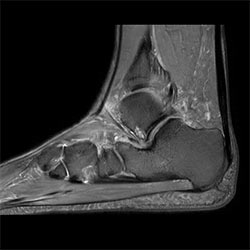

In a society where reimbursements are declining and chronic conditions lead to increased MR procedures and longer waiting times, there is ever increasing pressure on the radiology department. Today, further attempts to accelerate, compromise image quality or are limited to a narrow range of scans. Therefore, to meet the increased demand for productivity, a technology break-through in acceleration is still required. Leveraging our long standing leadership position in speed (i.e. SENSE), Philips brings compressed SENSE, a breakthrough in productivity.

Our goal is to reduce scan time, but we want the same image quality as before”

Sabine Sartoretti, MD, Head of Neuroradiology, Institute of Radiology and Nuclear Medicine, Kantonsspital Winterthur, Switzerland

Learn more about the main principles of Compressed SENSE and how it introduces a paradigm shift in productivity, how Compressed SENSE was designed around image quality, and how it advances productivity for clinical MR imaging.